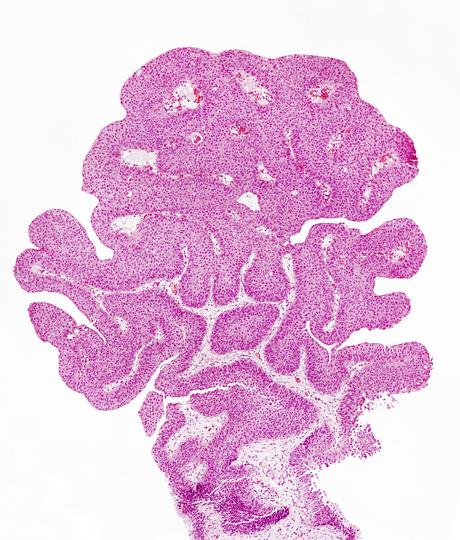

Le cancer urothélial est le type le plus courant de cancer de la vessie (90% des cas). Ce cancer peut se développer dans le bassin rénal (où l'urine s'accumule à l'intérieur du rein), dans l'uretère (tube qui relie les reins à la vessie) et l'urètre. L'un des traitements les plus largement utilisés est la chimiothérapie qui agit en ciblant toutes les cellules du corps, agissant avec succès sur les cellules cancéreuses, mais affecte également les cellules non cancéreuses, avec des effets secondaires.